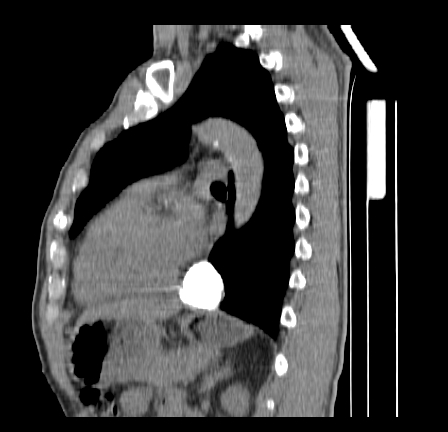

以下是引用影像孺子牛在2009-5-20 23:18:00的发言:[br]左侧后心膈角处类椭圆形钙化灶,最常见的是淋巴结钙化,但太大了不支持,其它如食管囊肿钙化、实性畸胆瘤等。何东西钙化真不好定。